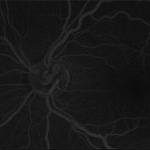

Late phase, ultra-wide fluorescein angiogram of a 53-year-old, African American male with history of diabetes, hypertension, depicting chronic hypertensive retinopathy changes and unilateral pre-papillary vascular loop OS.

Imaging device: Optos California

Condition/keywords: congenital prepapillary vascular anomaly, congenital prepapillary vascular loop, prepapillary vascular loop